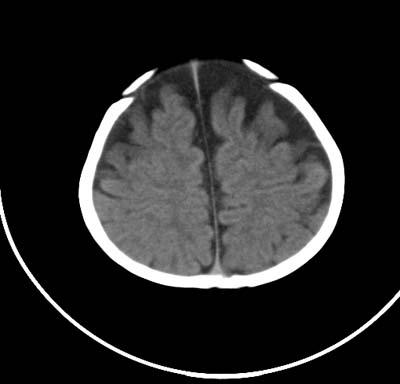

以下是引用影象小泰斗在2008-6-30 15:57:00的发言:[br]双侧额、颞部蛛网膜下腔增宽,纵裂加深, 支持外部性脑积水![br] 双侧基底节点状钙化!

以下是引用jiangjing在2008-6-30 17:19:00的发言:[br]双侧额、颞部蛛网膜下腔增宽,纵裂加深, 支持外部性脑积水![br] 双侧基底节点状钙化![宫内感染形成可能]